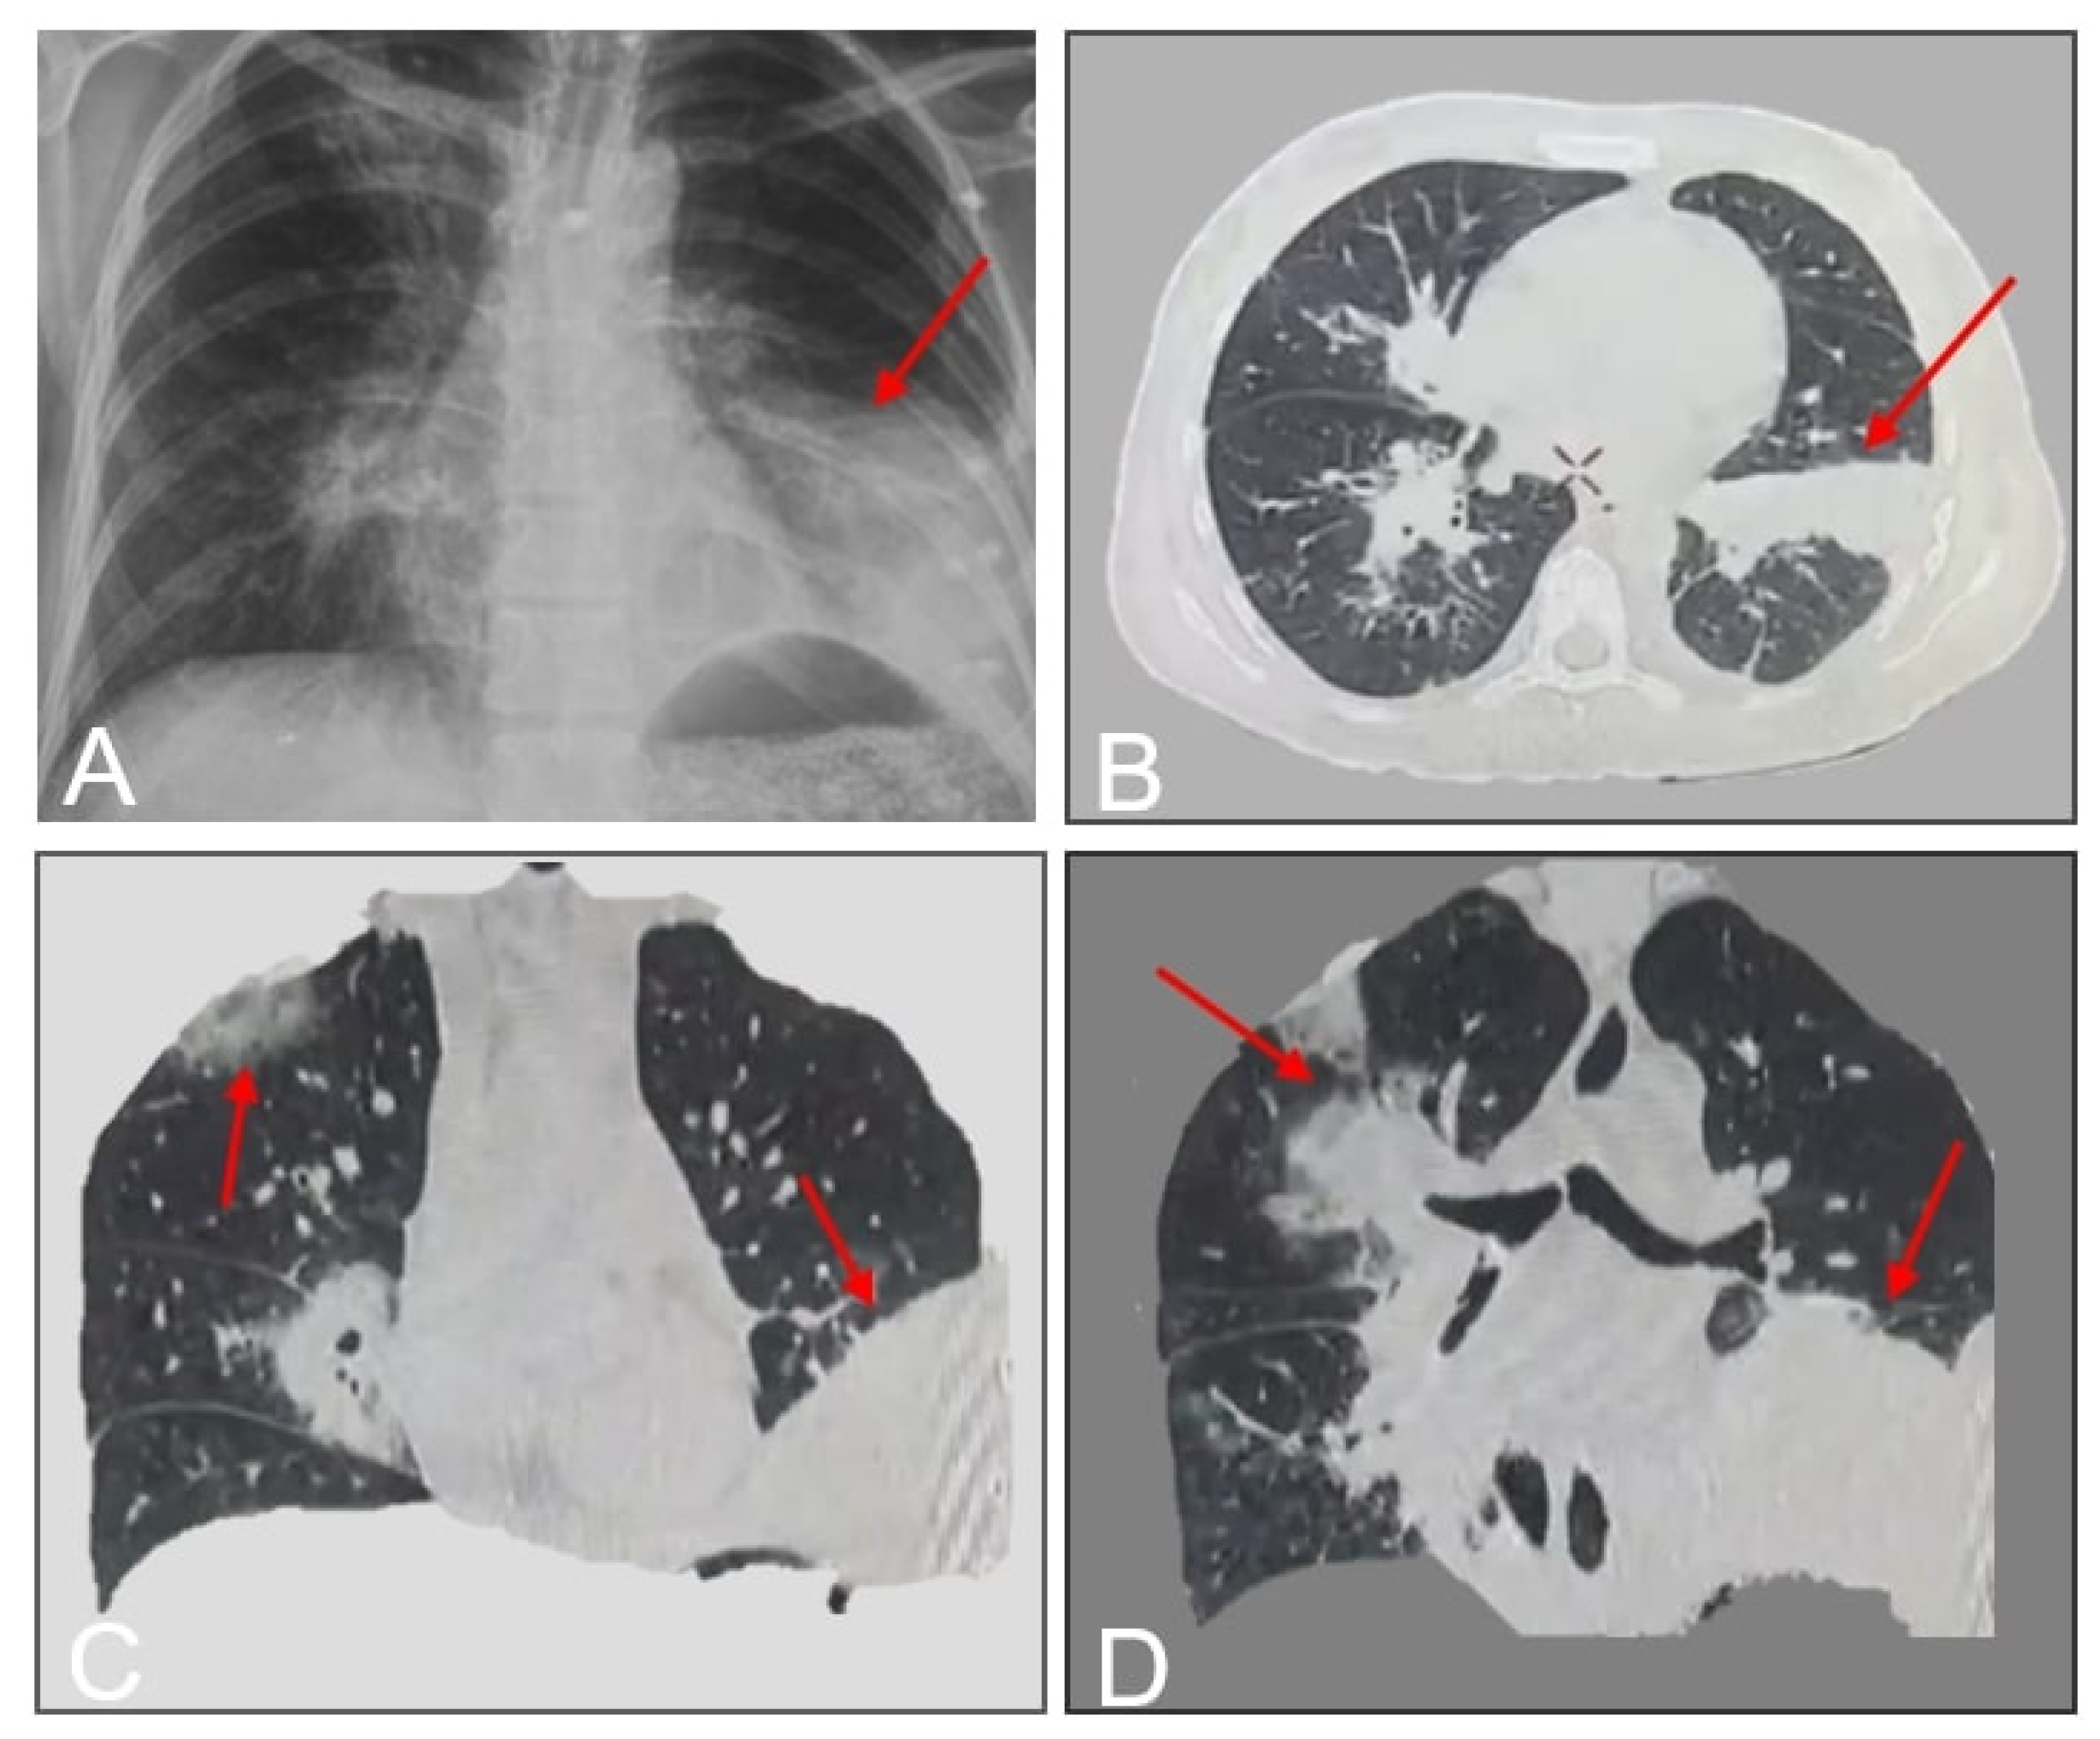

A 33-year-old female with poorly controlled type 1 diabetes mellitus (T1DM) and hypothyroidism presented with a 10-day history of fever, dry cough, pleuritic chest pain, and progressive dyspnea. Initial outpatient management with oral antibiotics (unspecified) failed to alleviate symptoms. On day 12 of symptom onset, she was hospitalized at a rural facility, where she developed hemoptysis and worsening respiratory distress. Laboratory studies confirmed diabetic ketoacidosis (DKA), and imaging suggested pneumonia. Due to clinical deterioration and lack of diagnostic resolution, she was transferred to our tertiary care center. On admission (day 12), the patient exhibited hypoxia (SpO2 89% on room air), tachypnea, and diminished breath sounds over the left hemithorax. Chest CT revealed left lower lobe consolidation with basal predominance (Figure 1).

Our patient developed pulmonary mucormycosis complications—bronchopleural fistula (BPF) and abscess—within 10 days of referral, aligning with reported median BPF onset timelines (8–12 days) [10,11,12,13]. Initial nonspecific symptoms (progressive dyspnea, pleuritic pain) and antibiotic-refractory pneumonia prompted exclusion of bacterial/viral etiologies via negative sputum cultures, pleural fluid analysis, and SARS-CoV-2/influenza RT-PCR. Chest radiography revealed lobar consolidation and cavitation, consistent with prior studies (consolidation: 43%, cavitation: 30%) [4,5,6,7,8]. Contrast-enhanced thoracic CT, the gold standard for assessing pulmonary mucormycosis (PM) [5], demonstrated ground-glass opacities, bronchial thickening, and BPF-related features (Figure 1, Figure 2 and Figure 3). Classic findings such as the “halo sign” (nodule encircled by ground-glass opacity) and vascular thrombosis leading to pulmonary infarction [3,4,5,6] were absent, though disease extension into adjacent structures (e.g., pleura) was evident.

Figure 1. A. Anteroposterior chest radiograph demonstrating left lower lobe consolidation with preserved hilar architecture. B. Axial contrast-enhanced chest CT (mediastinal window) revealing bilateral consolidative lesions (arrows), a cavitary abscess (asterisk) in the left lower lobe, and a bronchopleural fistulous tract (arrowhead). C-D. Coronal CT reconstructions (lung window) highlighting left basal consolidation (star) and right apical segment involvement (dashed circle), suggestive of multifocal angioinvasive disease.